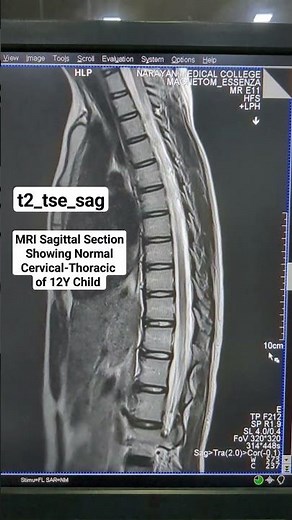

MRI Sagittal Section View Showing Normal Cervical-Thoracic Spine Sequence Planning #beginners

Medical Advanced Radiology

3K views

Jan 13, 2024

MRI Sagittal Section View Showing Normal Cervical-Thoracic Spine Seq

YouTube

Medical Advanced Radiology Knowledge